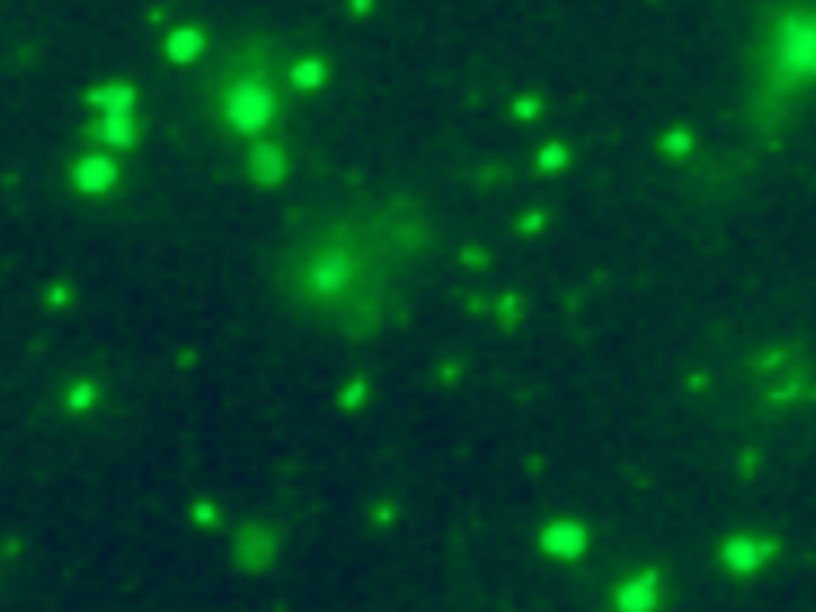

В новом исследовании Ален Тьерри и его коллеги, проанализировав плазму крови ста человек, обнаружили, что митохондриальная ДНК в ней находится внутри частиц размером более 0,22 мкм, содержащих специфические белки митохондриальной мембраны. Изучение их под электронным микроскопом показало, что у них имеются и другие признаки митохондрий: наличие внешней и внутренней мембран, характерная внутренняя структура. В результате ученые пришли к выводу, что эти частицы представляют собой неповрежденные митохондрии, существующие вне клеток. Анализ потребления кислорода показал, что эти митохондрии способны осуществлять свои обычные функции.